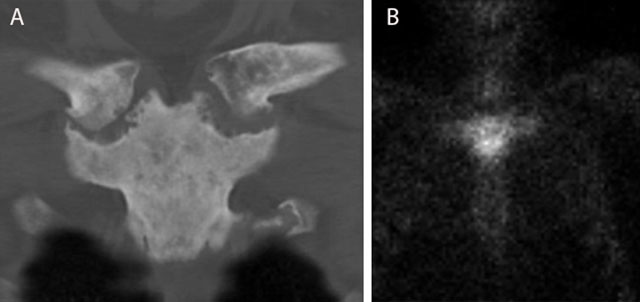

Figure 14

Typical bullhead sign in SAPHO of the sternoclavicular joint. CT (coronal reformatted image) (a) shows sclerosis of the manubrium sterni and medial clavicles and erosions of the sternoclavicular joints. Note a typical bullhead sign on scintigraphy (b).